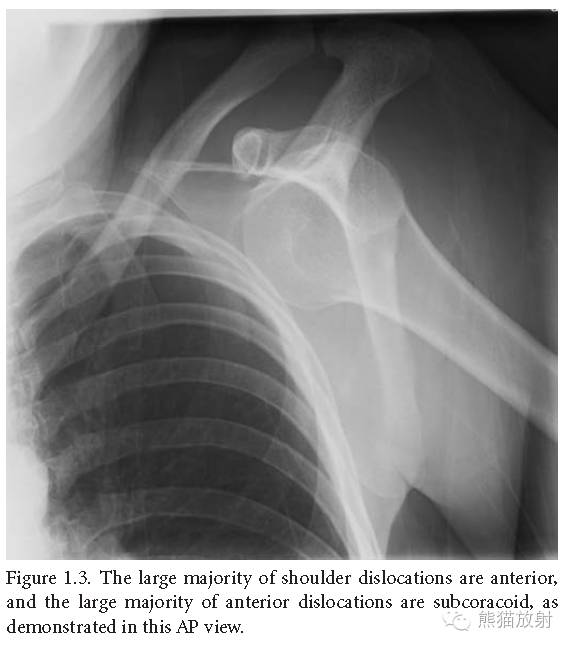

肩关节脱位中大部分是前脱位,前脱位中大部分是喙突下脱位(如上正位片中所示)。